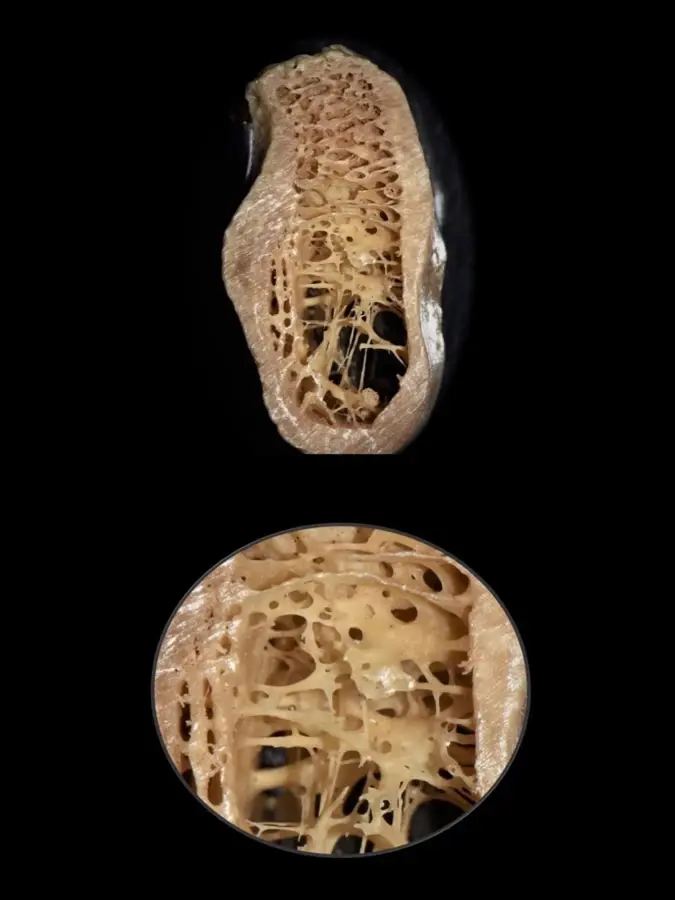

Durante años, se establecieron las propiedades biomecánicas del hueso basándose únicamente en medidas a gran escala, pudiendo diferenciarse entre el hueso trabecular y el hueso cortical. Sin embargo, actualmente es posible un mayor análisis a nivel micrométrico que permite explorar entre los componentes orgánicos, tisulares, celular y moleculares. Es así que gracias a aproximaciones nanoestructurales se muestran asociaciones entre las propiedades biomecánicas y las calidades óseas, las que se pueden presentar tanto en el hueso cortical como en el trabecular de manera indistinta. En el cortical, el espacio poroso ocupa el 5-10%, mientras que en el trabecular se encuentra en el 30-90% del total de la estructura9 (Figura 1).

Figura 1. Sector postero-inferior de la mandíbula donde se aprecia una cortical gruesa y hueso esponjoso con espacios medulares amplios (arriba) y trabéculas bastante finas (debajo), muchas veces del espesor de un cabello (0,025 mm).